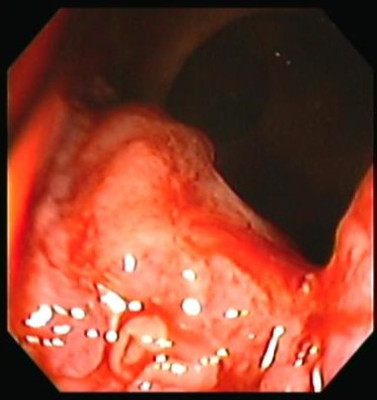

Cáncer de Colon

Envíado por Dr. Carlos Ernesto Arévalo